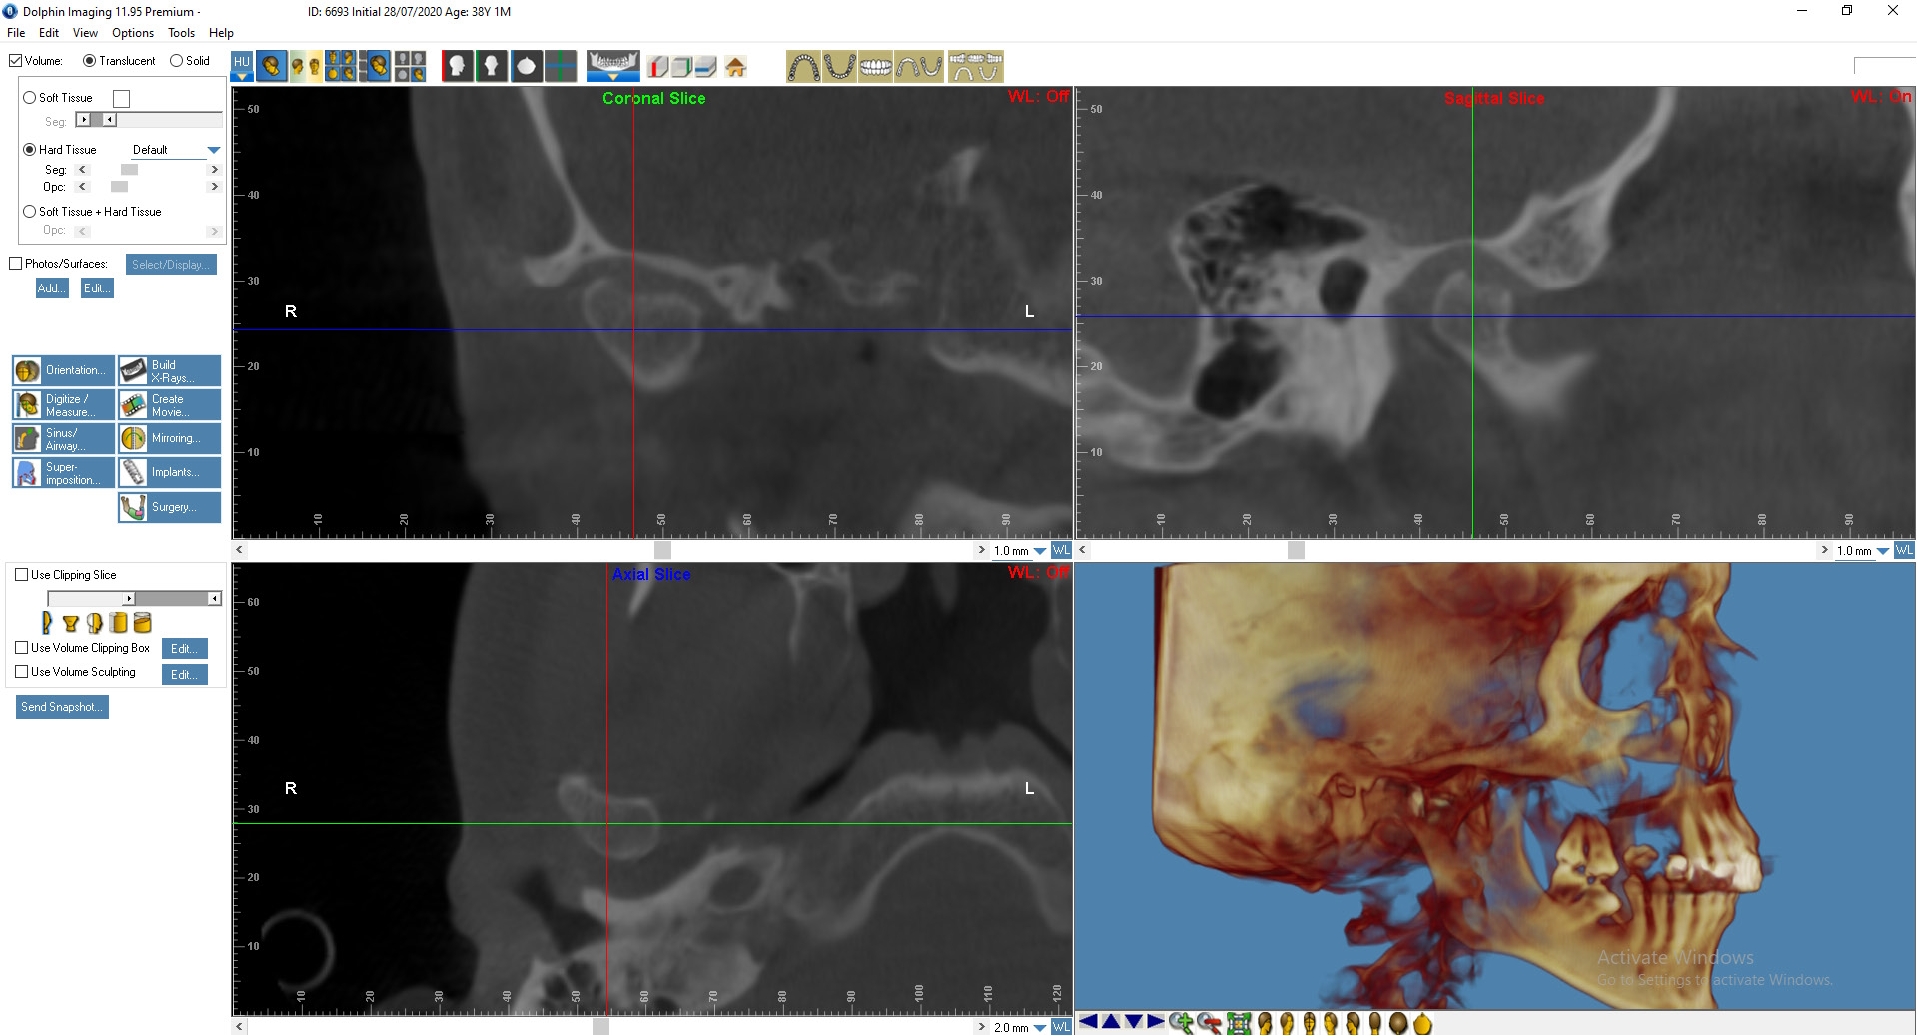

На основании КТ с использованием лицензионной программы Dolphin Imaging 11.95 Premium определяли цефалометрические параметры черепа и анатомические изменения в ВНЧС. Для интерпретации результатов МРТ использовали Radiant Dicom Viewer.

Лечение: Пациенту Д. была выполнена окклюзиограмма, на основании которой были устранены супраконтакты методом избирательного пришлифовывания зубов. Также было выполнено лечение сплинт-терапией для восстановления работы височно-челюстного сустава. Фиксирована брекет-система на зубы нижней челюсти (рис. 3, 4).

По данным МРТ ВНЧС спустя 2 года после начала лечения отмечается устранение вентро-латеральной дислокации суставного диска в положении привычной окклюзии. Также устранен синовит, увеличился объем движения в суставе (рис. 5). Как видно из рис. 4 и 5, по данным КТ ВНЧС спустя 2 года после начала лечения отмечается ремоделирование головки нижней челюсти. Клинически увеличилось открывание рта до 38 мм.

Рис. 4. Пациент Д., 38 лет. КТ ВНЧС до начала лечения